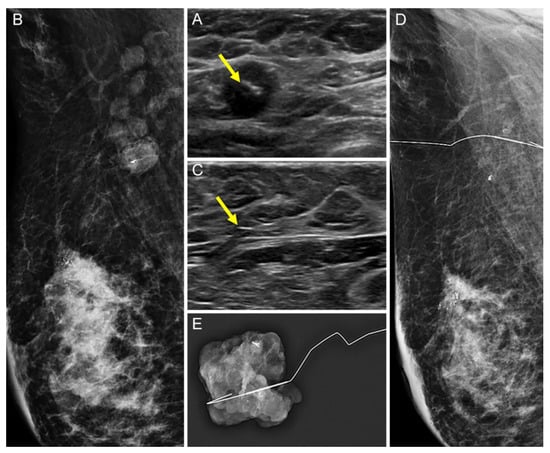

Comparison of the Ultrasound Visibility of Tissue Markers in Metastatic Lymph Nodes after Neoadjuvant Chemotherapy in Patients with Breast Cancer

3.1. Comparison of the US Visibility between the Two Tissue Markers after NAC

3.2. Comparison of the Successful Excision Rates of the Clipped Lymph Nodes between the Two Tissue Markers